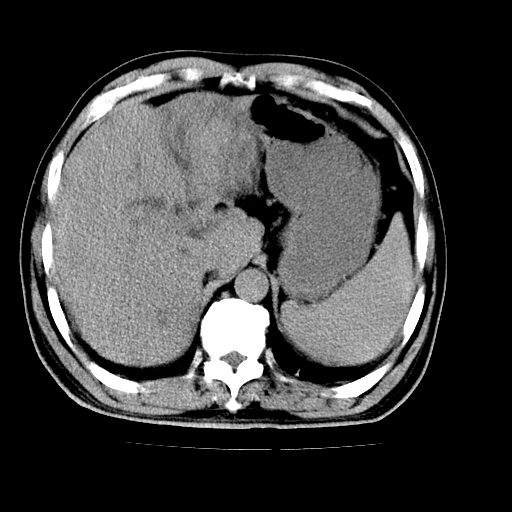

男,66岁,上腹部不适、黄染一周。彩超示:肝左叶占位,肝内胆管扩张,胆总管扩张,胆总管占位?

肝左叶不规则软组织肿块影,边缘不规整邻近肝实质受累分界不清;肝内胆管(左叶)明显扩张成“软藤状”,诊断:肝左叶胆管细胞癌。

肝左叶占位性病变,并胆管扩张,符合胆管细胞癌ct表现,门脉左支受累,左肾囊肿。窗宽太窄了,其他的看不清

左叶胆管细胞癌累及胆总管,门脉左支受侵,慢性胆囊炎胆结石,左肾小囊肿